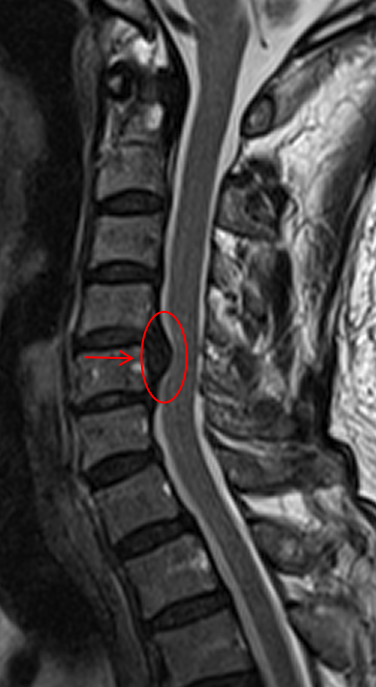

內(nèi)鏡輔助下的微創(chuàng)ACDF手術(shù)

1. 視野更清晰:內(nèi)鏡能將手術(shù)區(qū)域的神經(jīng)和血管放大十倍,顯示在高清屏幕上,更有利于醫(yī)生精準(zhǔn)實施手術(shù)。

2. 操作更精細(xì):在放大視野下,可以毫厘不差地移除壓迫神經(jīng)的突出物,最大程度避免了對正常神經(jīng)的干擾。

術(shù)后頸椎MR